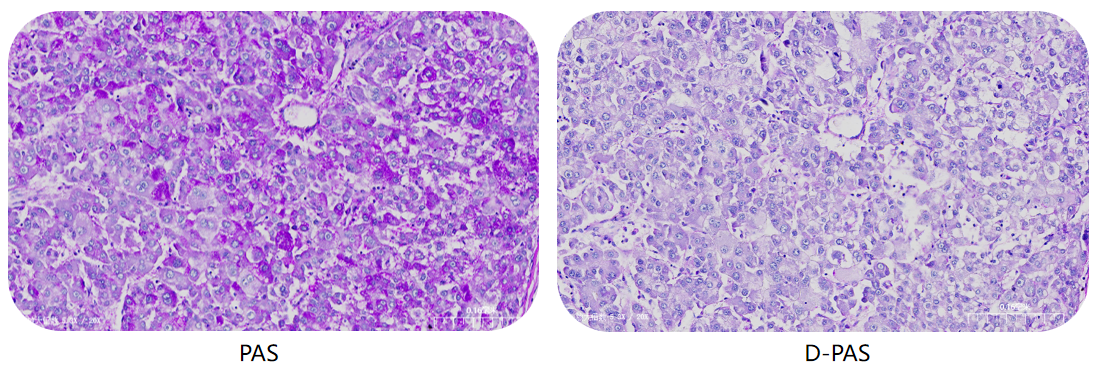

Periodic Acid-Schiff (PAS) Stain Kit

· Clinical Applications: Detects glycogen, mucin, and fungal cell walls; commonly used in diagnosing glycogen storage diseases, fungal infections, and certain tumors such as hepatocellular carcinoma or renal cell carcinoma.

Periodic Acid-Schiff (PAS) Diastase Kit

· Clinical Applications: Differentiates glycogen from other PAS-positive substances through enzymatic digestion; essential for confirming glycogen-containing lesions or excluding glycogen in diagnostic samples.